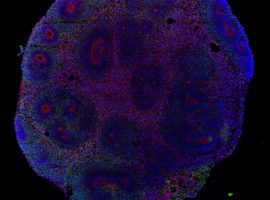

Stevens Rehen é um neurocientista do Instituto D’Or de Pesquisa e Ensino (IDOR) no Brasil e atua como Pesquisador Associado na Promega Corporation e no Instituto Usona. Ele é Membro Afiliado da Academia de Ciências da América Latina e da Academia de Ciências do Mundo em Desenvolvimento (TWAS). Entre suas honrarias estão a Ordem Nacional do Mérito Científico (Comendador, Brasil) e a Bolsa do Programa Latino-Americano PEW em Ciências Biomédicas. Ele detém um cargo não remunerado de professor na Universidade Federal do Rio de Janeiro e foi reconhecido com o Prêmio Internacional Fiocruz Servier para Neurociências e o Prêmio Fulbright de Professor Visitante. Stevens Rehen também foi Presidente da Sociedade Brasileira de Neurociências e Comportamento. Seu foco principal de pesquisa é sobre os efeitos dos psicodélicos em organoides cerebrais humanos e Caenorhabditis elegans.

Palavras-chave: células-tronco de pluripotência induzida (iPSC); organoides cerebrais; neuroesferas; neurociência; vírus Zika

Karmirian K, Holubiec M, Goto-Silva L, Fernandez Bessone I, Vitória G, Mello B, Alloatti M, Vanderborght B, Falzone TL, Rehen S. Modeling Alzheimer’s Disease Using Human Brain Organoids. Methods Mol Biol. 2023;2561:135-158. PMID: 36399268.

N. Costa M, Goto-Silva L, M. Nascimento J, Domith I, Karmirian K, Feilding A, Trindade P, Martins-de-Souza D, K. Rehen S. LSD Modulates Proteins Involved in Cell Proteostasis, Energy Metabolism and Neuroplasticity in Human Cerebral Organoids. ACS Omega. (2024).

Salerno JA, Rehen S. Human pluripotent stem cells as a translational toolkit in psychedelic research in vitro. iScience. 2024 Mar 28;27(5):109631. PMID: 38628967; PMCID: PMC11019282.